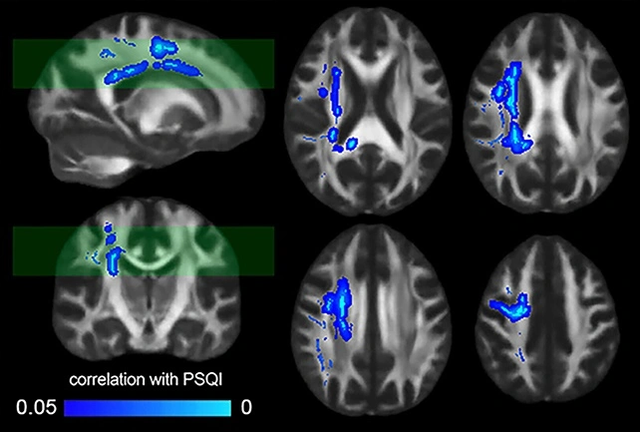

Në fazën e parë të studimit, ekipi analizoi skanimet me rezonancë magnetike (MRI) të trurit të 185 vullnetarëve të shëndetshëm, raporton Science Alert. Rezultatet konfirmuan provat e mëparshme se integriteti i lëndës së bardhë cerebrale bie kur pjesëmarrësit raportojnë cilësi të dobët të gjumit.